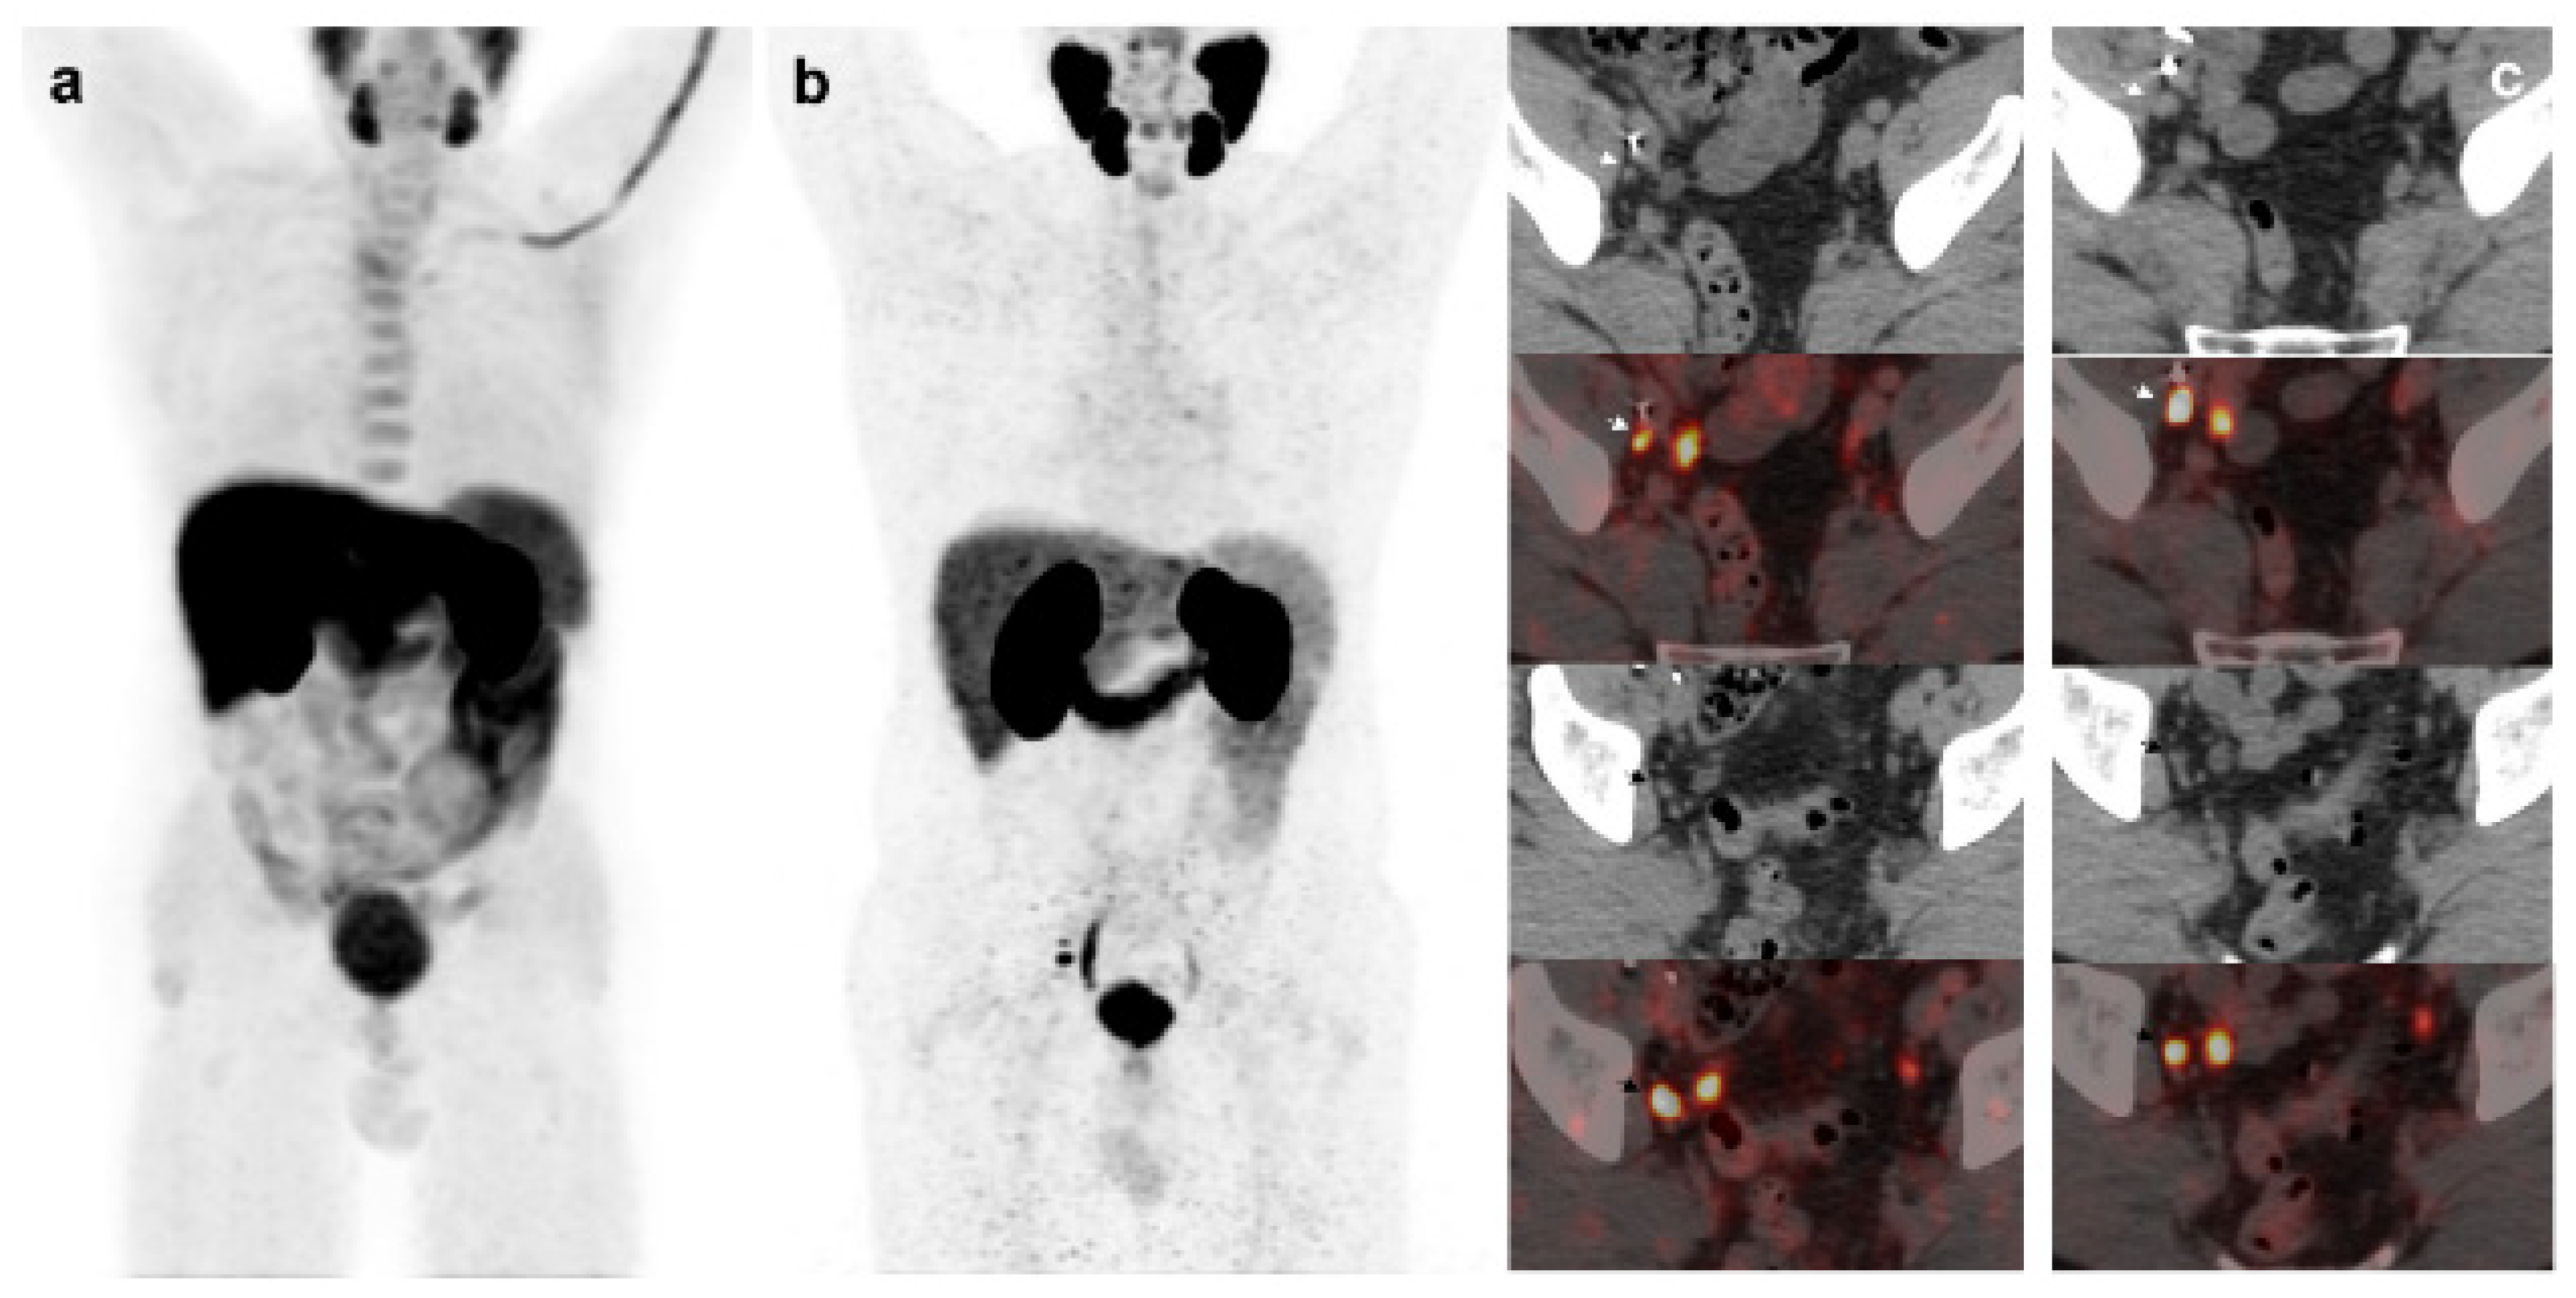

Derived from positive 18F-DCFPyL-PET/CT, 19 patients underwent additional diagnostic procedures to confirm the results: 8 by imaging (3/8 was confirmed) and 11 by histological analysis (8/11 was confirmed) (Figure 3) (Figure 4).

Figure 3. 55-year-old patient. Gleason 8 PCa treated with RP. First BCR treated with prostate fossa radiotherapy. Second BCR (PSA: 0.84 ng/mL, PSAdt 5.99 mo, PSAvel 0.07 ng/mL/mo). 18F-Fluorocholine-PET/CT negative (a). 18F-DCFPyL-PET/CT (b), time window of twenty days, revealed two right external iliac lymph node metastasis (arrows). Lymphadenectomy was decided (escalation), without histopathological confirmation of malignancy. In follow-up PSA progressed (2.07 ng/mL) and an additional 18F-DCFPyL-PET/CT (c) showed exactly same lymph nodes (arrows). SBRT was administered decreasing the PSA level, reclassifying 18F-DCFPyL-PET/CT results as true positive.